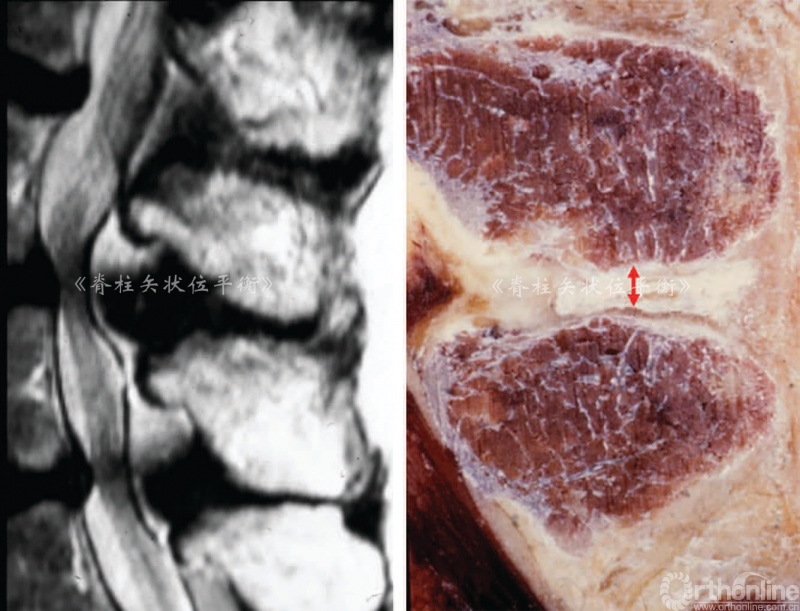

人类的衰老退变是不可避免的,而且可能受到遗传因素和机械因素的影响(脊柱限制性的专业运动或重复性的体育运动)而加速。椎间盘在18岁的时候开始脱水变性,这可以引起生理性腰椎前凸减小(图1),L5~S1减小25°, L4~L5减小15°,上腰椎减小1°~2°。

图1 随着老龄化,下腰椎椎间盘扁平,关节突及棘突增宽,导致腰前凸角度减小